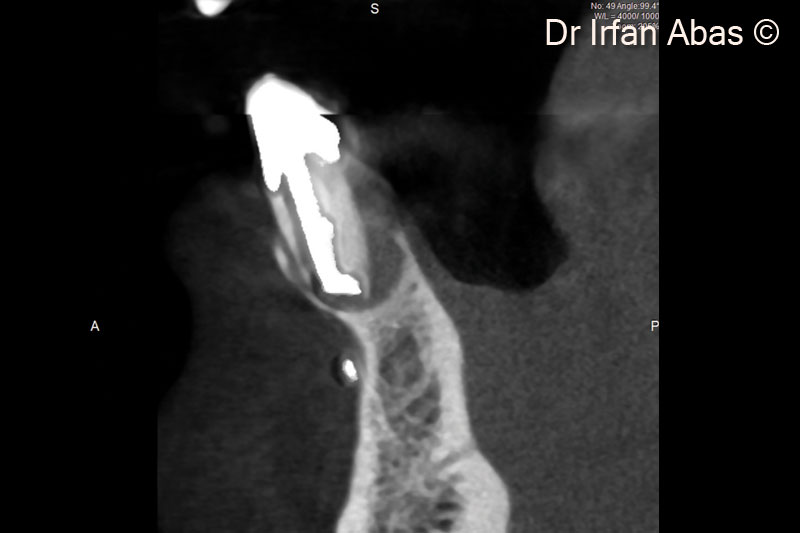

2. The CBCT shows a lingual and palatal bone defect